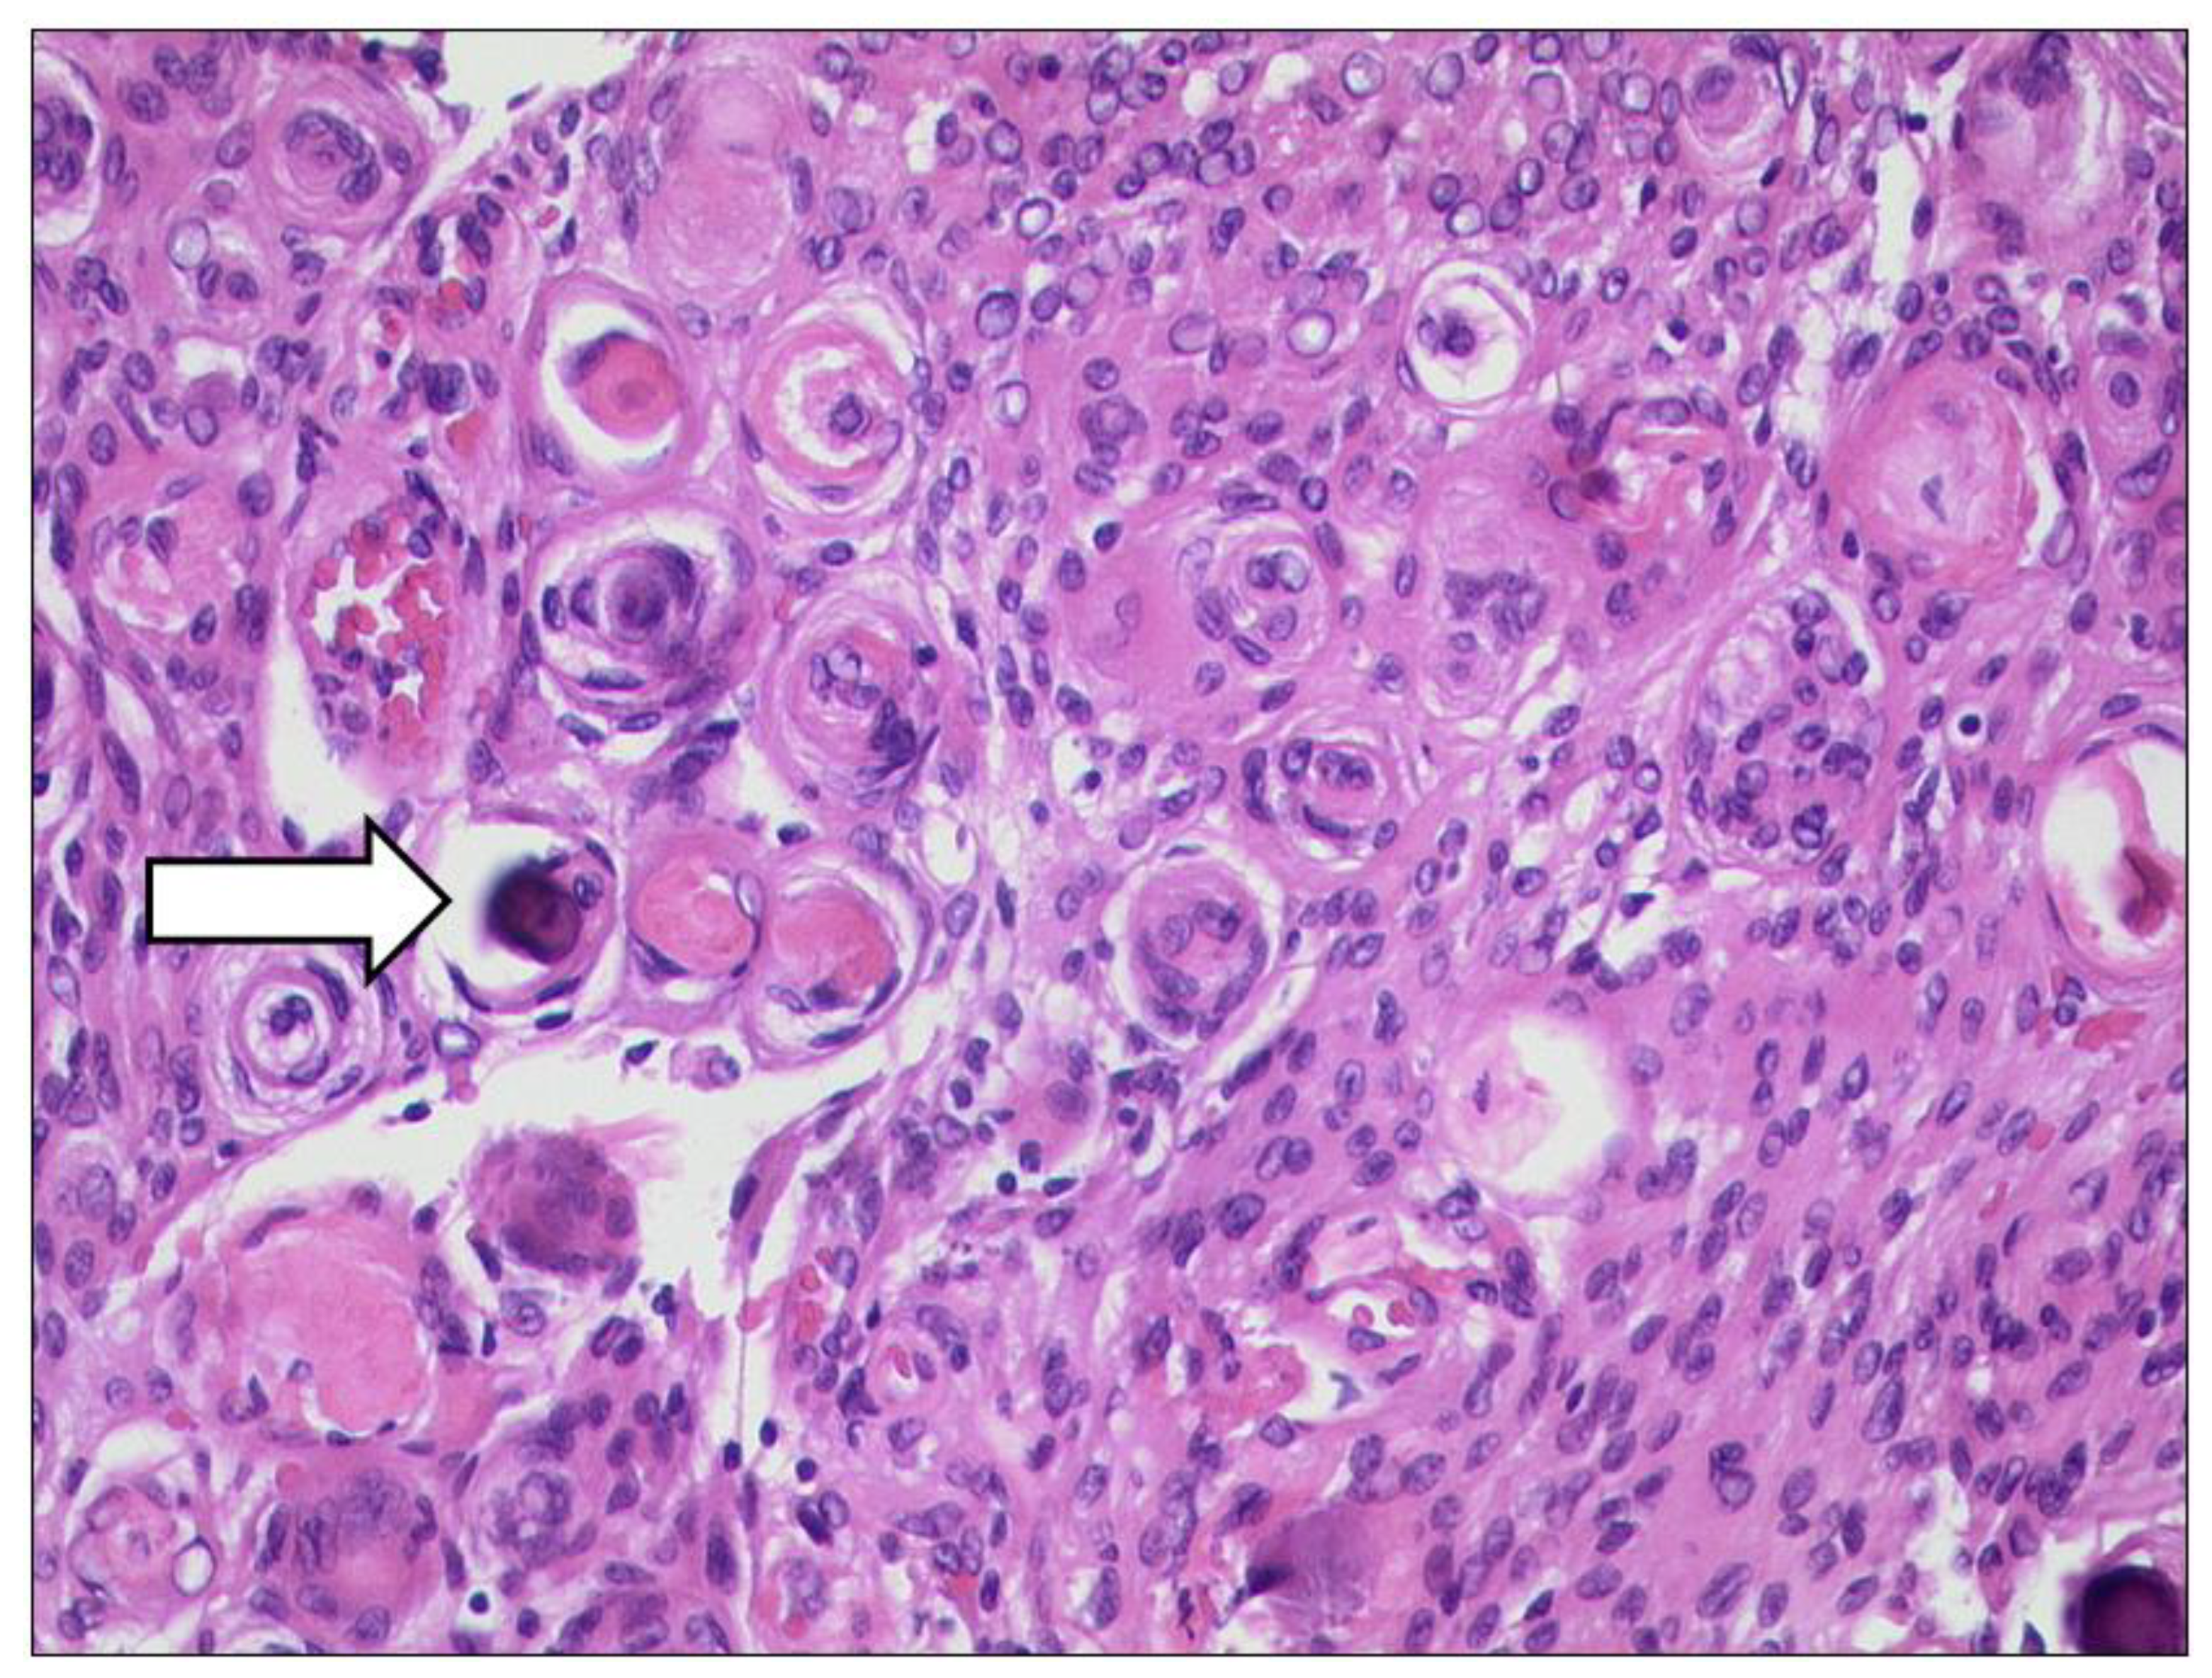

3.6.2. Rhabdomyosarcoma